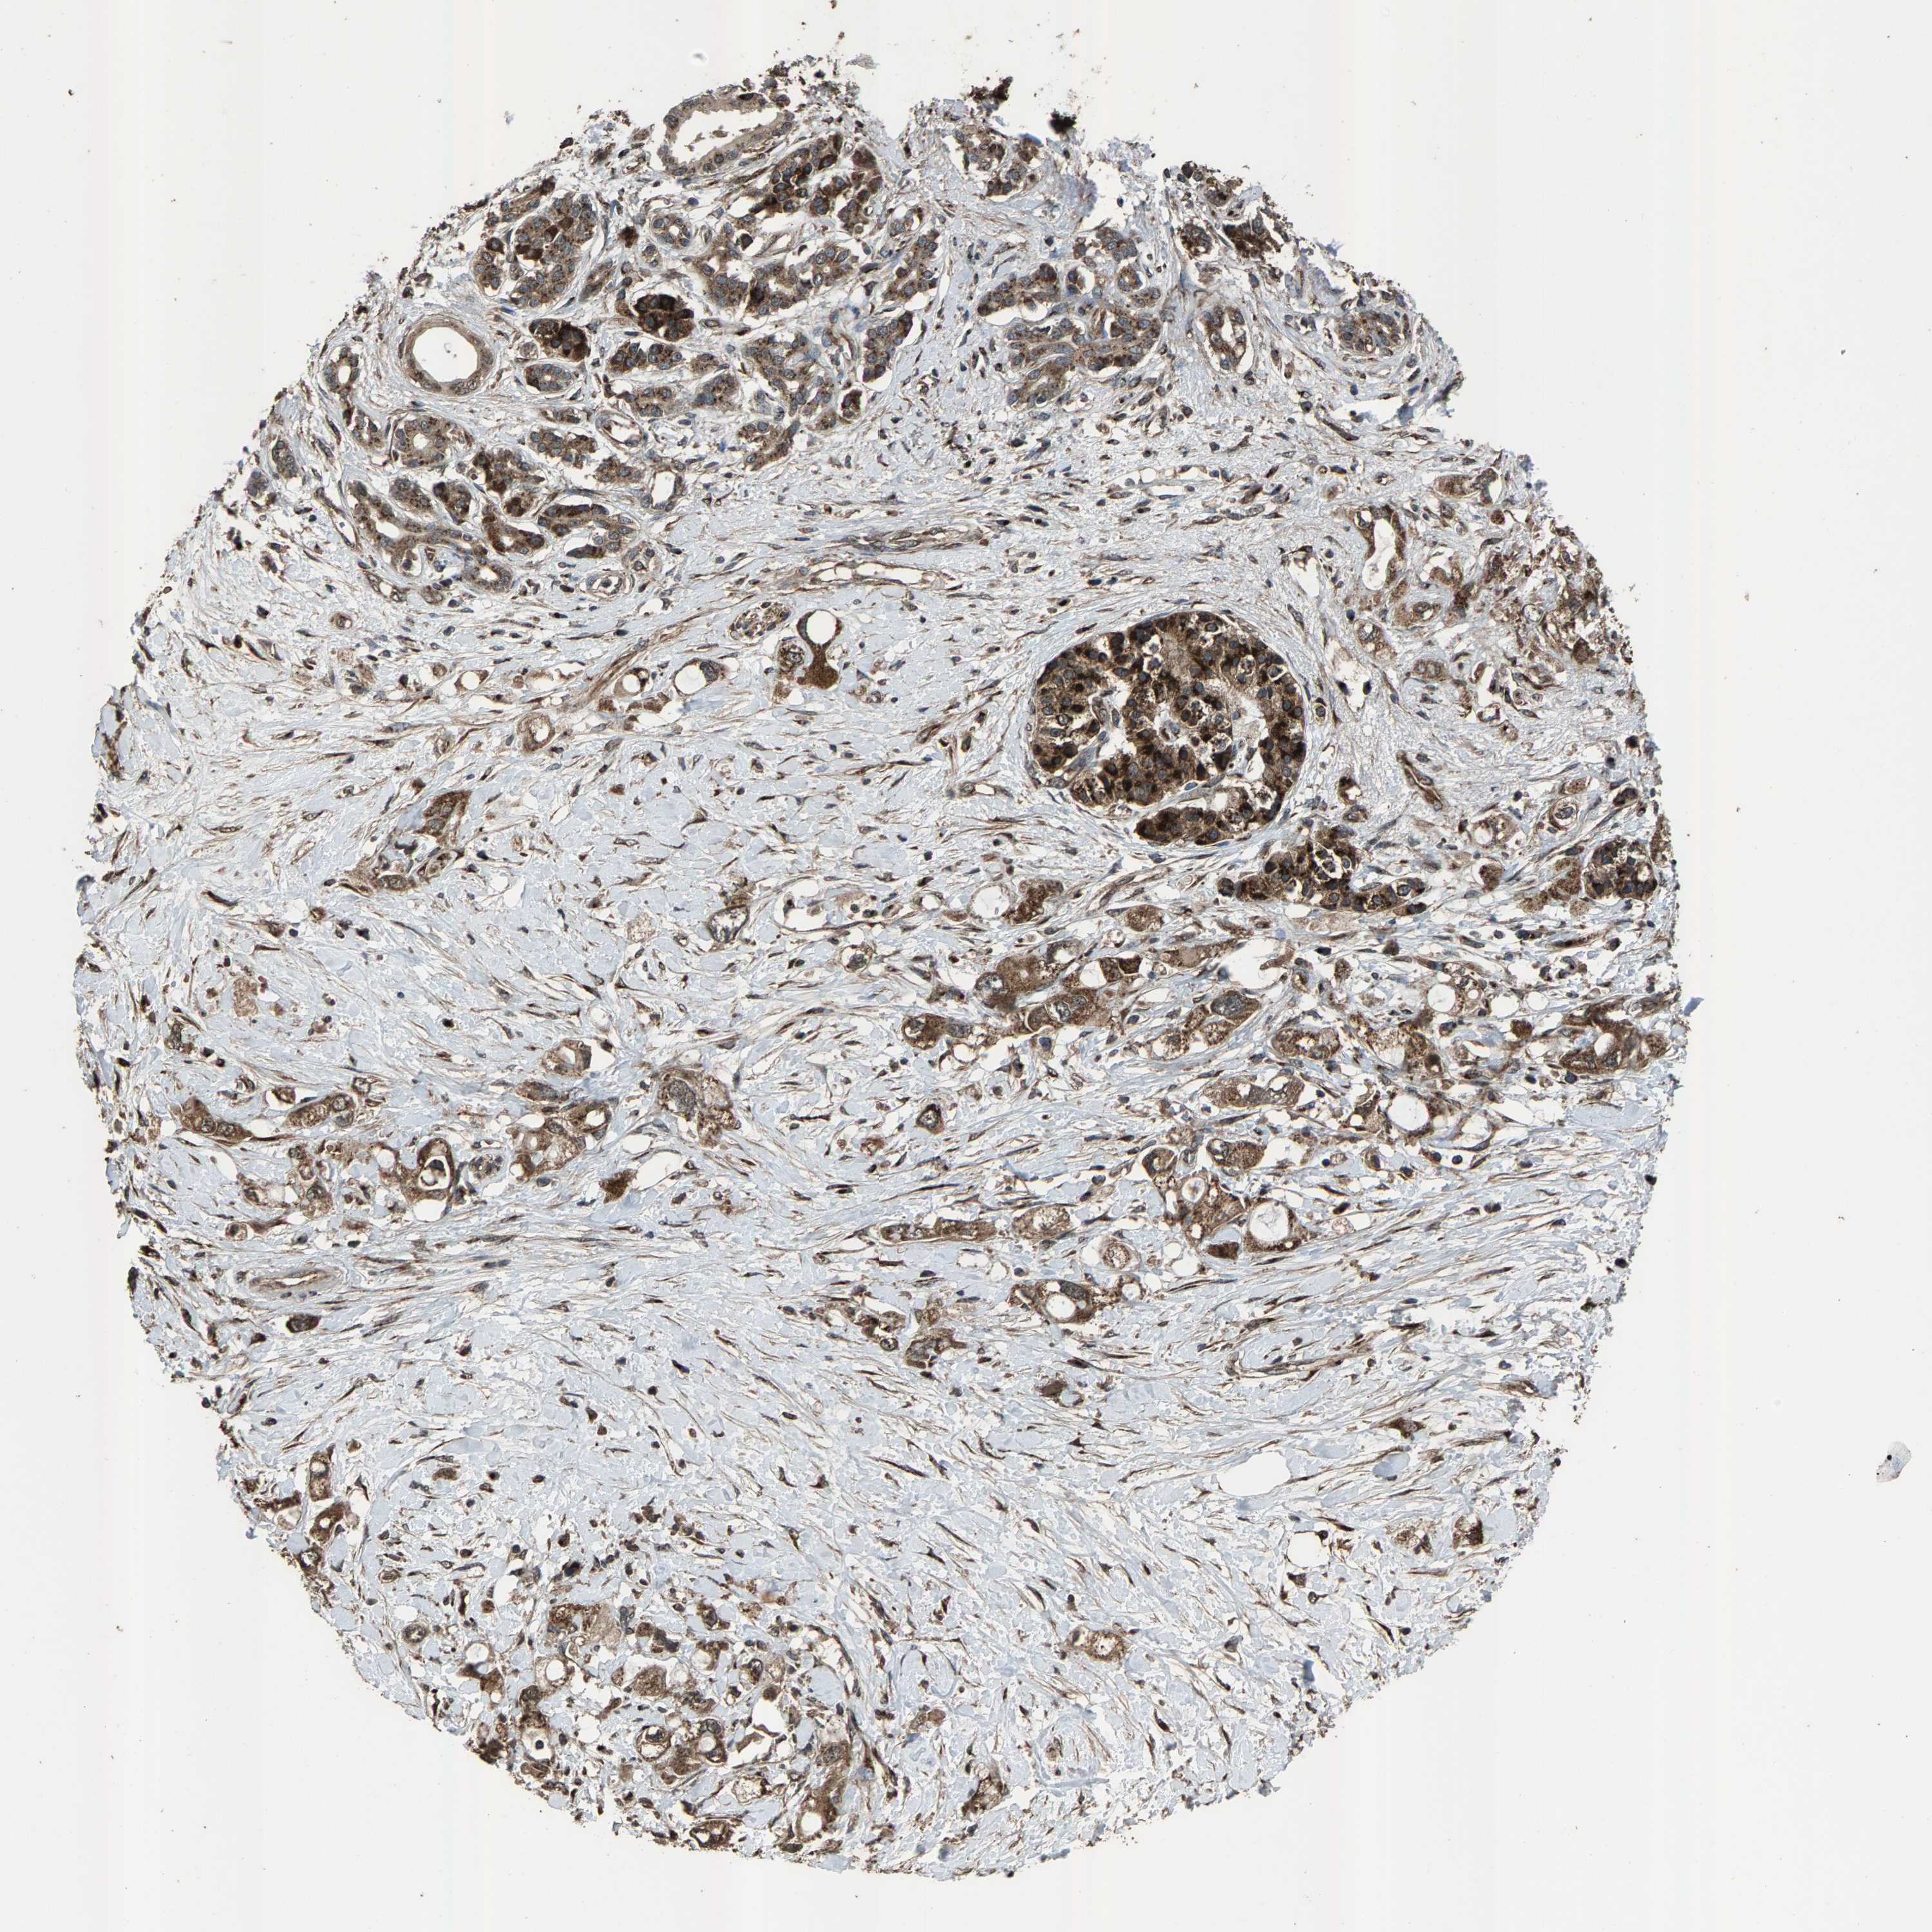

PANCREATIC CANCER - Protein expressioni

A mouse-over function shows sample information and annotation data. Click on an image to view it in a full screen mode. Samples can be filtered based on level of antibody staining by selecting one or several of the following categories: high, medium, low and not detected. The assay and annotation is described here.

Note that samples used for immunohistochemistry by the Human Protein Atlas do not correspond to samples in the TCGA dataset.

Antibody stainingi

Antibody staining in the annotated cell types in the current human tissue is reported as not detected, low, medium, or high, based on conventional immunohistochemistry profiling in selected tissues. This score is based on the combination of the staining intensity and fraction of stained cells.

Each image is clickable and will lead to virtual microscopy that enables deeper exploration of all samples and also displays staining intensity scores, fraction scores and subcellular localization as well as patient and tissue information for each sample.

Antibody HPA021374

Antibody HPA023161

Antibody HPA024631

Staining

High

Medium

Low

Not detected

Intensity

Strong

Moderate

Weak

Negative

Quantity

>75%

75%-25%

<25%

None

Location

Nuclear

Cytoplasmic/membranous

Cytoplasmic/membranous,nuclear

Adenocarcinoma, NOS